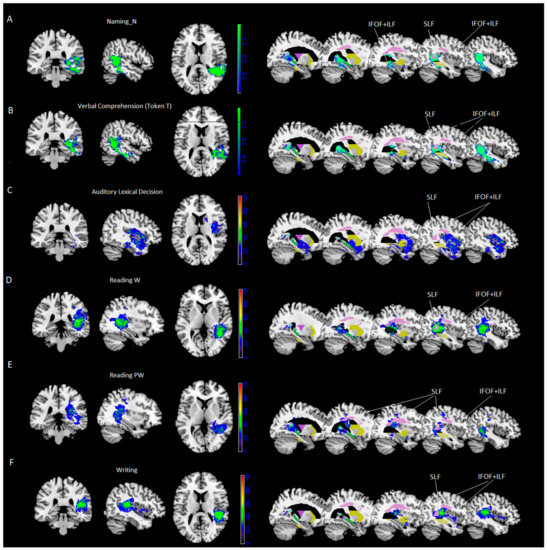

- Results of VLSM analyses were significant for noun naming and verbal comprehension (Token Test) only. VLSM performed for noun naming revealed 24% of the voxels damaged in the middle temporal cortex and, to a lesser extent (between 15% and 10%), in the inferior and superior temporal gyrus, the hippocampus/parahippocampal area and the fusiform gyrus (Figure 1A). In addition, at subcortical level we found portions of the posterior thalamic radiation and the sagittal stratum [including the inferior fronto-occipital fasciculus (IFOF) and the inferior longitudinal fasciculus (ILF)], with 40% of overlapping lesions, and to a lesser extent (% voxels damaged between 29% and 14%), the retrolenticular part of the internal capsule, the superior longitudinal fasciculus (SLF, with 50% of overlapping lesions) and pars of the tapetum (see Table 4 and Figure 1A).

- VLSM analyses performed for the Token Test revealed 26% of the voxels damaged in the middle temporal cortex and, to a lesser extent (between 15% and 10% of the voxel damaged), in the inferior and superior temporal gyrus, and the hippocampus (Figure 1B). At subcortical level we found parts of the sagittal stratum (including IFOF and ILF, with 43% of overlapping lesions), posterior corona radiate and posterior thalamic radiation and the retrolenticular part of the internal capsule, pars of the tapetum and, to a lesser extent (% voxels damaged between 26% and 5%), the superior longitudinal fasciculus (SLF, with 49% of overlapping lesions) and pars of the splenium (see Table 4 and Figure 1B).

- for word reading, performed by 55/85 patients: in the superior temporal gyrus (57%) and, at subcortical level, in the superior longitudinal fasciculus (57%), the posterior thalamic radiation and the retrolenticular part of the internal capsule (47% and 44%) and the sagittal stratum (including IFOF and ILF, 36%);

- for pseudo-word reading, performed by 55/85 patients: in the calcarine cortex and the middle and inferior temporal gyrus (37%) and, at subcortical level, in the posterior thalamic radiation (39%), in the SLF (37%) and the retrolenticular part of the internal capsule and the tapetum (37%);

- for auditory lexical decision, performed by 41/85 patients: in the superior temporal gyrus (40%) and, at subcortical level, in the sagittal stratum (including IFOF and ILF, 36%);

- for writing, performed by 46/85 patients: in the superior temporal gyrus (58%) and, at subcortical level, in the SLF (45%).